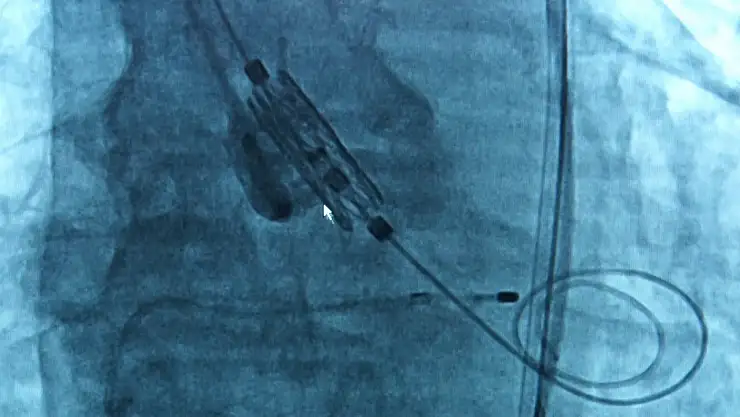

Aort kapağının zamanla kireçlenip daraldığını ve bunun kalbin yeterli kan pompalamasını engellediğini anlatan Doç. Dr. Karabulut, “Kapak darlığı nedeniyle gelişen nefes darlığı, bayılma, çabuk yorulma gibi semptomlar zamanla kalp yetmezliğine kadar ilerleyebilir. Bu durumda iki temel tedavi yöntemimiz bulunuyor. Biri klasik açık cerrahiyle kapak değişimi, diğeri ise TAVI yöntemi. TAVI, kasıktan girilerek yapılan kapalı bir işlemdir ve hastanın göğüs kafesi açılmadan uygulanır” dedi.

Cerrahiye alternatif olarak geliştirilen TAVI’nin artık yalnızca ameliyat olamayan değil, orta ve hatta düşük riskli hastalara da uygulanabildiğini ifade eden Karabulut, işlemin yaklaşık 1 saat sürdüğünü ve hastaların genellikle ertesi gün taburcu edildiğini aktardı.

Uzm. Dr. Ersan Oflar ise TAVI işlemlerinde yeni nesil kapak teknolojilerinin tercih edildiğini, bu kapakların hem hekime hizalama açısından kolaylık sağladığını hem de işlem sonrası kalıcı pil ihtiyacını azalttığını söyledi. Oflar, “Kapak doğru pozisyonda yerleştirilmezse, ileriki dönemde daha çabuk bozulabiliyor. Yeni nesil kapaklar bu konuda avantaj sunuyor” dedi.